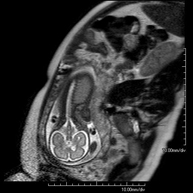

Prova diagnòstica no invasiva que consisteix en l'obtenció d'imatges d'alta definició anatòmica del fetus en la dona gestant mitjançant l'ús d'un camp electromagnètic i ones de ràdio (amb un emissor i un receptor). No utilitza radiació ionitzant. Es pot realitzar a partir de la dotzena setmana de gestació, essent segura tant per al fetus com per a la mare. S'utilitza si se sospita d'alguna anomalia congènita morfològica. - RM Muscular